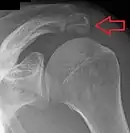

Os acromiale.

Shoulder:

• An os acromiale forms when any of its four ossification centers fail to fuse. These four ossification centers are called (from tip to base) pre-acromion, meso-acromion, meta-acromion, and basi-acromion. In most cases, the first three fuse at 15–18 years, whereas the base part fuses to the scapular spine at 12 years. Such failure to fuse occurs in between 1% and 15% of cases.[23][24] It rarely causes pain.